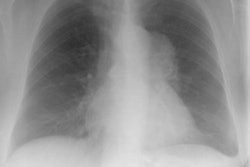

Intrathoracic lymphoproliferative disorders (LPDs) span a spectrum of benign lesions to those that are frankly malignant or have a malignant potential. The clonality of lymphoid populations is helpful in separating benign from malignant disorders. Polyclonality is usually reflective of benign disease, while monoclonality is usually indicative of malignancy. Stimulation of bronchus-associated lymphoid tissue (or BALT) and the Ebstein-Barr virus (EBV) are thought to play key roles in these disease processes. It has been postulated that the EBV genome may act as a stimulant, either as a primary or reactivated agent, particularly in disorders such as infectious mononucleosis and the post-transplant lymphoproliferative disorder.

Several generalizations have been made regarding the LPDs. These are: 1- older symptomatic patients have a more aggressive disease (i.e., lymphoma); 2- benign LPDs tend to be focal (i.e., lung or lymph nodes) and pleural effusions are rare in benign disease; and 3- the post-transplant LPDs may have a variety of radiographic findings (i.e., infiltrates, masses, and/or adenopathy). The site of disease may also provide a clue to the diagnosis. Parenchymal lung abnormalities are found in association with plasma cell granuloma (pulmonary pseudotumor), pseudolyphoma, and lymphatoid granulomatosis (angiocentric immunoproliferative lesion). While mediastinal disease suggests Castleman's disease, infectious mononucleosis, or angioimmunoblastic lymphadenopathy.